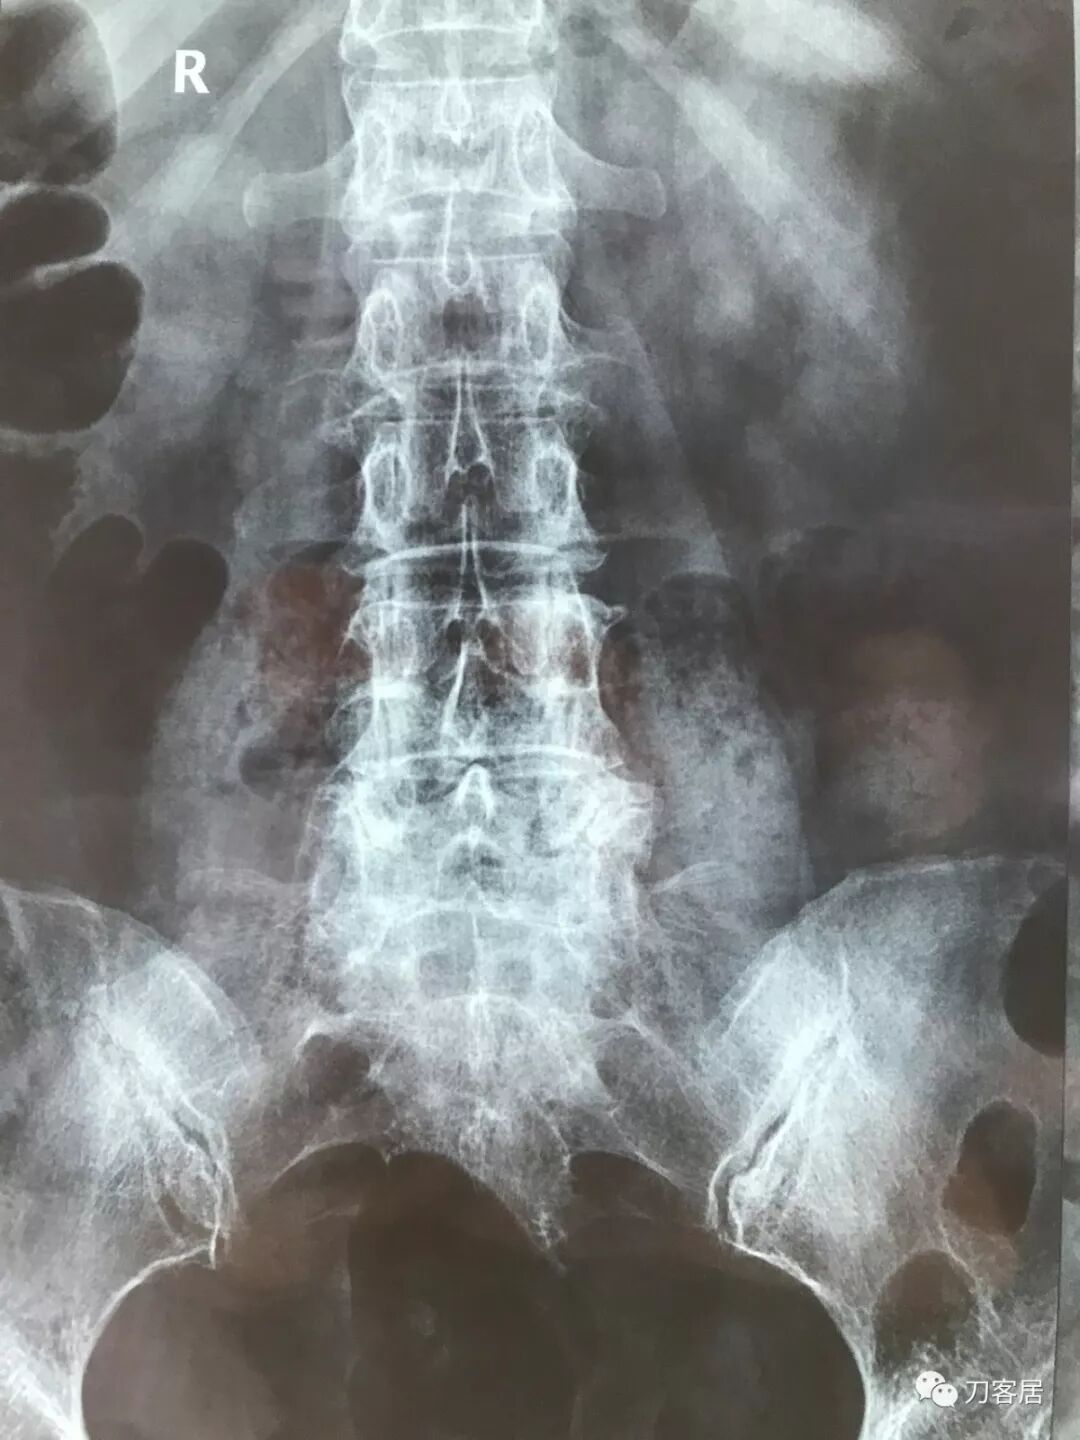

比如以下这几张翻拍图

倾斜、反光、透亮

对于医生阅片造成很大的阻碍

图1:倾斜

图4:倾斜